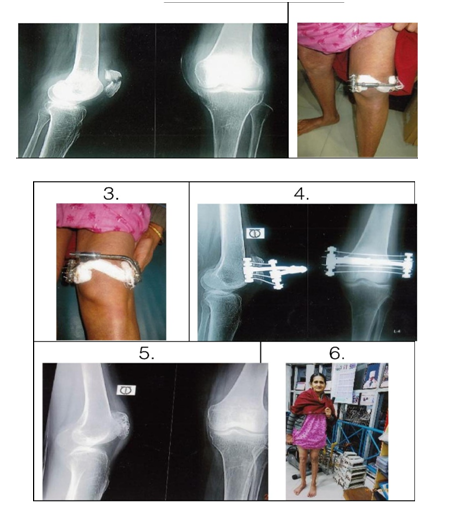

Sound union was achieved in all the fragments at an average of 6 to 8 weeks. That was proved clinically and radiologically. Knee flexion was 90° within 2 to 3 weeks and it was upto 120° by 4 weeks. The Insall knee score for patient function obtained on 12 patients was 96 points and 2 cases who did not carry our instructions, ultimately resulted in less than 90° arc of motion. Complications included 3 wire site inflammation which managed by local care. We found articular surface incongruity (>2m) because of incomplete primary reduction in 2 cases (Table 2). These two patients with articular incongruity developed patello-femoral osteoarthrosis after 2 years follow up postoperatively (Figure 2).

Figure 2 a. Radiograph of transverse fracture of left patella with displacement.

b. CEF in the left patella (2nd Post Op).

c. CEF in the left patella follow up after 3 weeks.

d. Radiograph of left patella with CEF in situ (After 3 weeks).

e. Radiographic final result of the patella after removal of CEF.

f. Smiling clinical appearance of the patient after treatment.